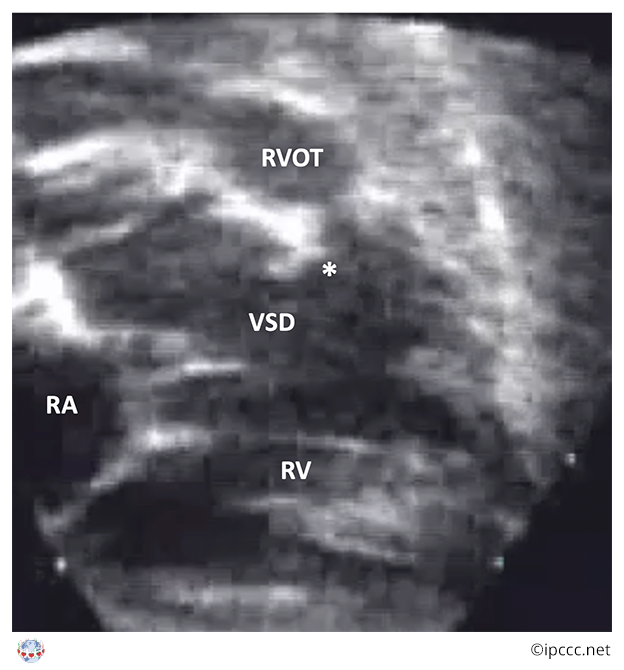

A group of congenital cardiac malformations with biventricular atrioventricular alignments or connections characterized by anterosuperior deviation of the conal or outlet septum or its fibrous remnant, narrowing or atresia of the pulmonary outflow, a ventricular septal defect of the malalignment type, and biventricular origin of the aorta. Tetralogy of Fallot will always have a ventricular septal defect, narrowing or atresia of the pulmonary outflow, aortic override, and most often right ventricular hypertrophy.

Echocardiogram